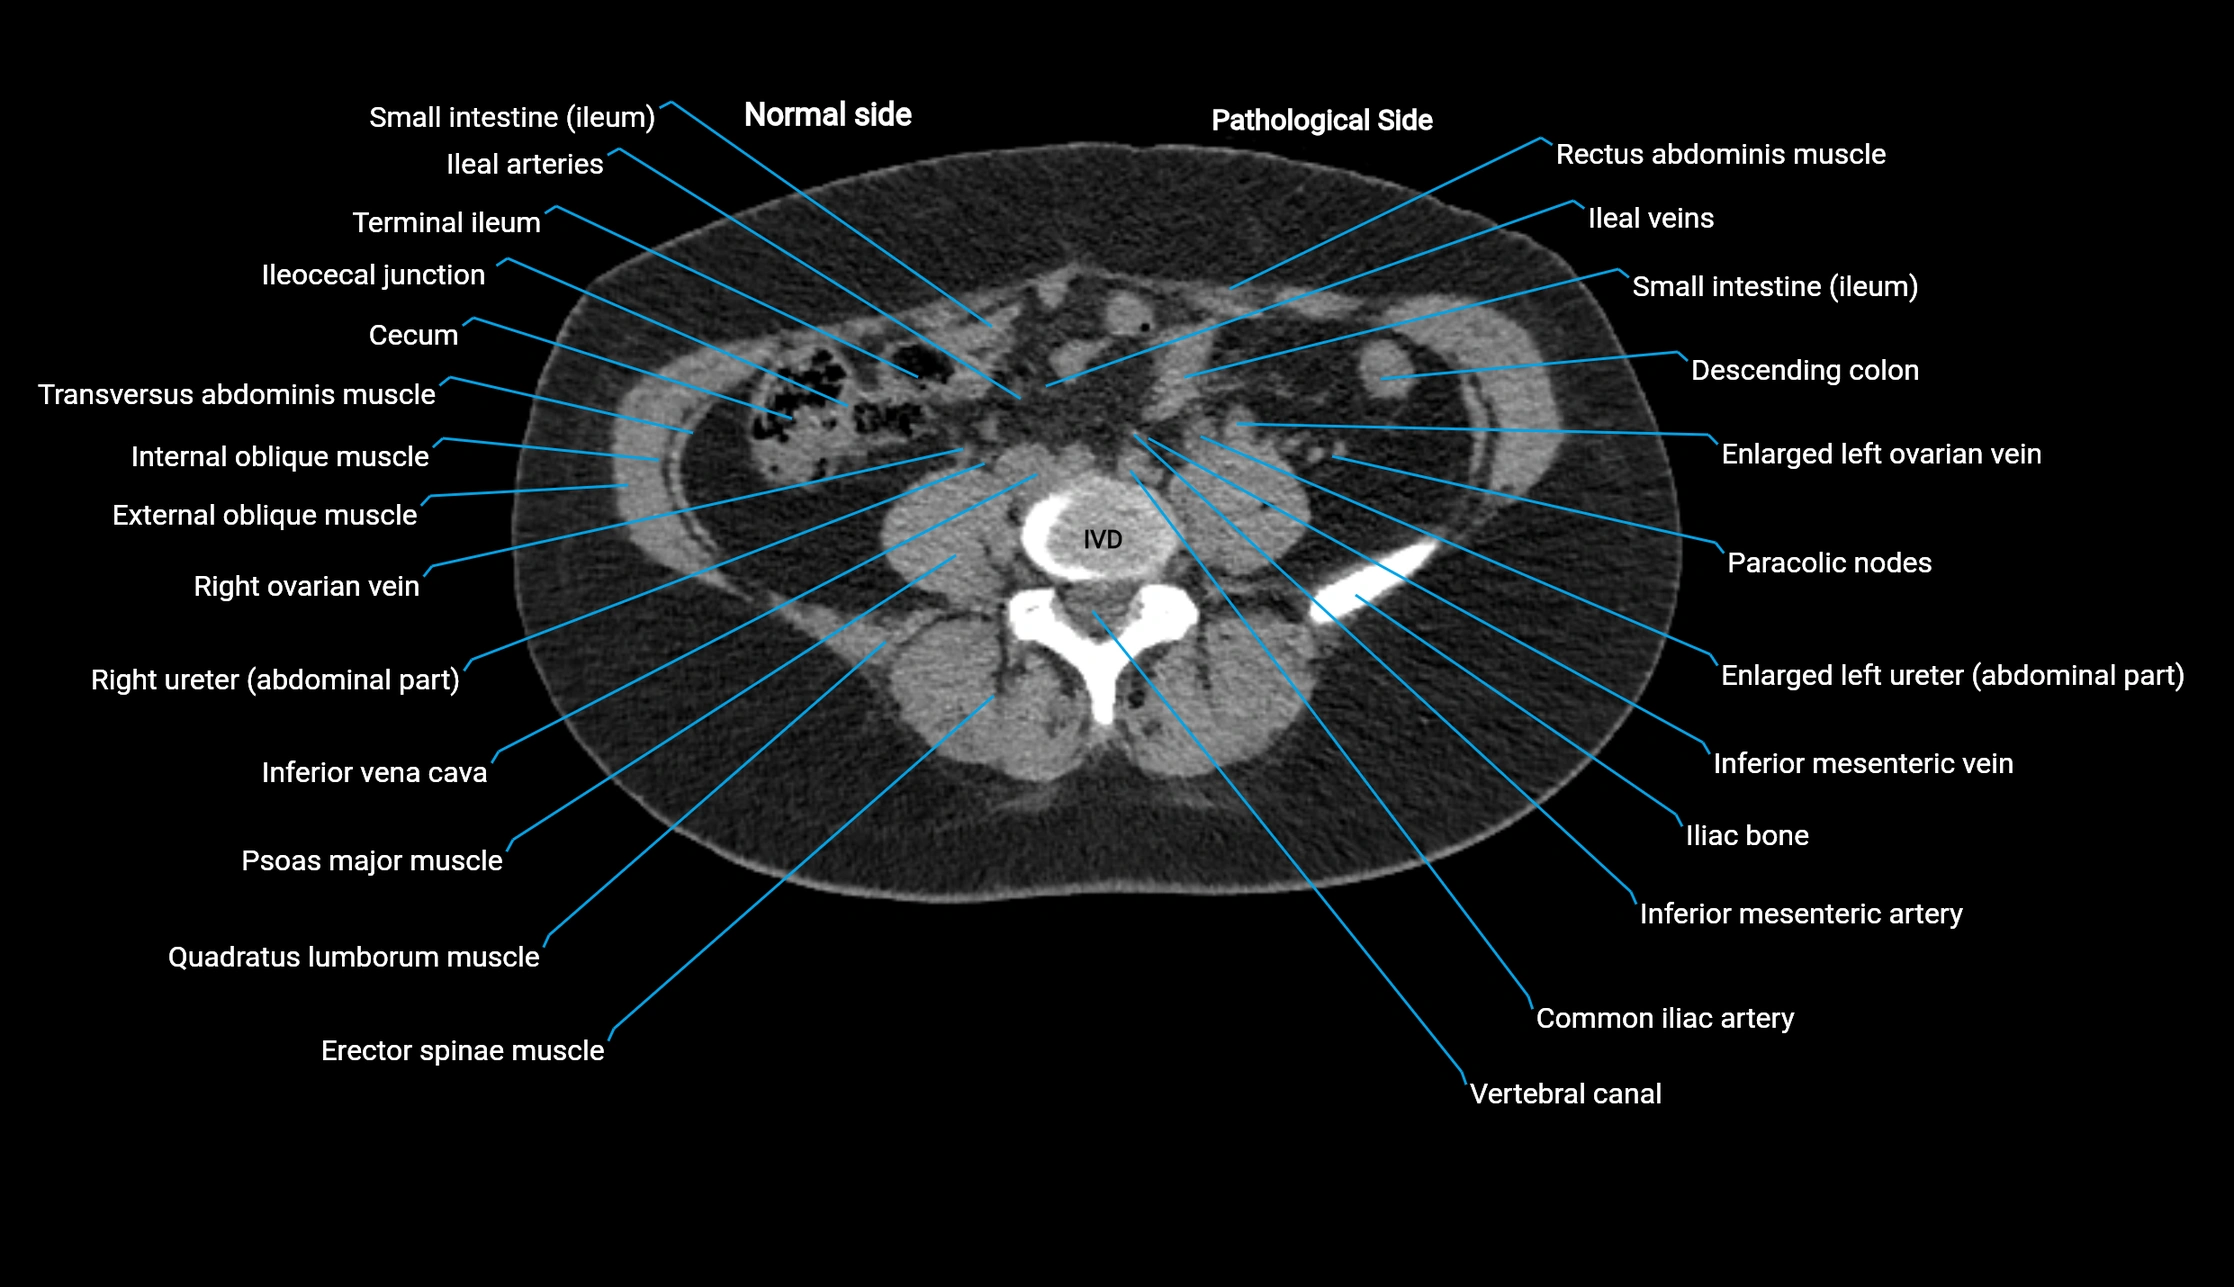

CT image

image